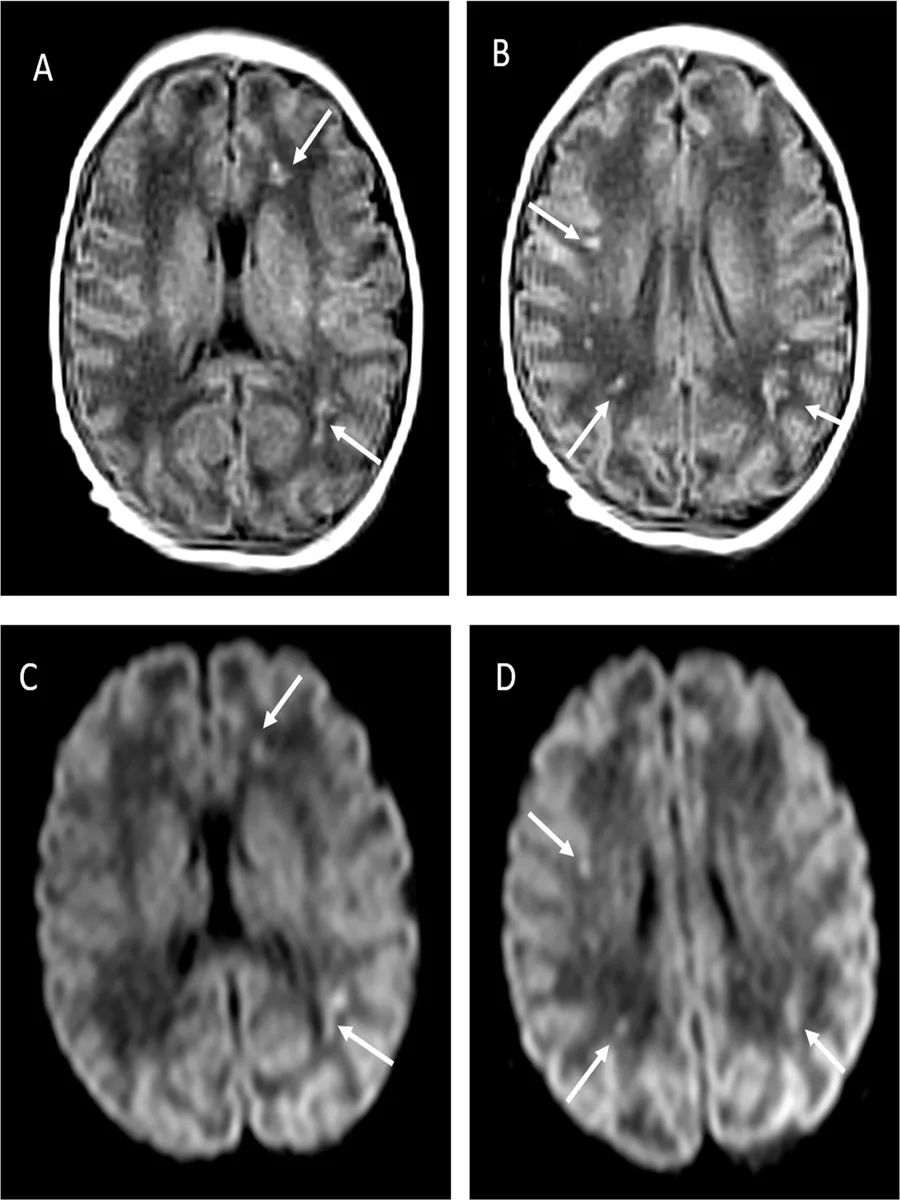

脑脊液SARS-CoV-2呈阴性,细菌、真菌、肠道病毒、单纯疱疹病毒1、2呈阴性,白细胞数为300个/mm3,蛋白轻度升高(1.49 g/L)。血培养无菌。脑超声和脑电图也正常。排除代谢性疾病可能。症状在3天内缓慢改善,第5天第二次脑脊液检查正常。磁共振显示双侧脑室周围和皮质下胶质增生。

本次随访至2个月后,神经系统检查进一步改善(高血压改善,运动功能正常),磁共振成像(白质损伤减轻);生长和其余临床检查均正常。